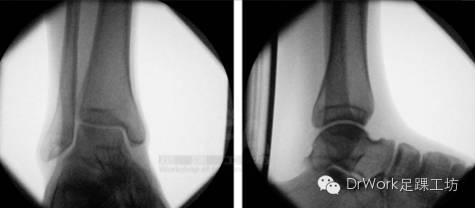

术中Hook试验

• 目前最佳诊断方法

• 矢状面移位较冠状位移位更显著

• 100N左右外力较合适

• 过大未提高准确率

• TFCS>5mm即可诊断不稳

• 术中复位后正位片、侧位片与健侧对比